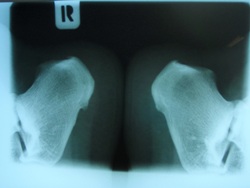

Calcaneum

2 views RM60

View of both calcanei

showing a right calcaneal spur